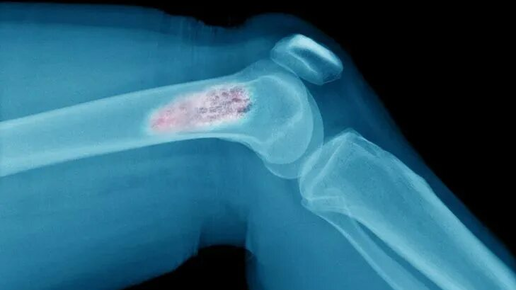

Рак костей тоже бывает: почему он развивается и влияют ли на его возникновение переломы и травмы

Рак костей — это редкое, но серьезное заболевание, которое требует внимания и понимания. Несмотря на то, что он составляет менее 1% от всех случаев онкологии, его последствия могут быть весьма тяжелыми. Основная проблема заключается в том, что рак костей часто сложно распознать на ранних стадиях. Это может привести к неправильной диагностике и затруднениям в лечении. В этом тексте мы подробно рассмотрим, что такое рак костей, почему он возникает, каковы его симптомы и методы диагностики. Рак костей может быть первичным или вторичным...